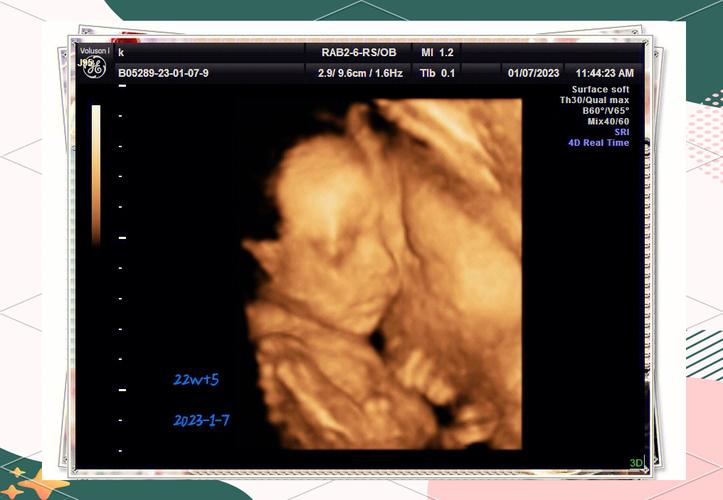

在人類生命的起始階段,一個奇妙而複雜的連結構築了新生命賴以生存的基礎。這條連結不僅提供了養分,更是母體與胎兒之間無可取代的生命橋樑。當我們談到「臍帶跟什麼連在一起」時,其答案遠不止一個簡單的器官名稱,它包含了一整套精密的生理系統,確保了胎兒在子宮內安全地成長發育。

要回答「臍帶跟什麼連在一起」這個核心問題,最直接的答案就是胎盤(Placenta)。臍帶,這條看似簡單的管狀結構,實則是連接胎兒腹部與母體胎盤的專屬生命線。